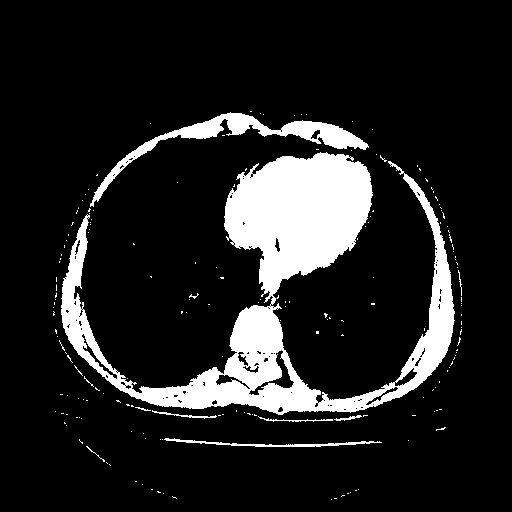

Generated VENOUS CT scan (A→B translation)

Full window (WL 1023.5, WW 4095 β†’ Low βˆ’1024, High +3071)

Actual HU range: [-1024.0, 3071.0]